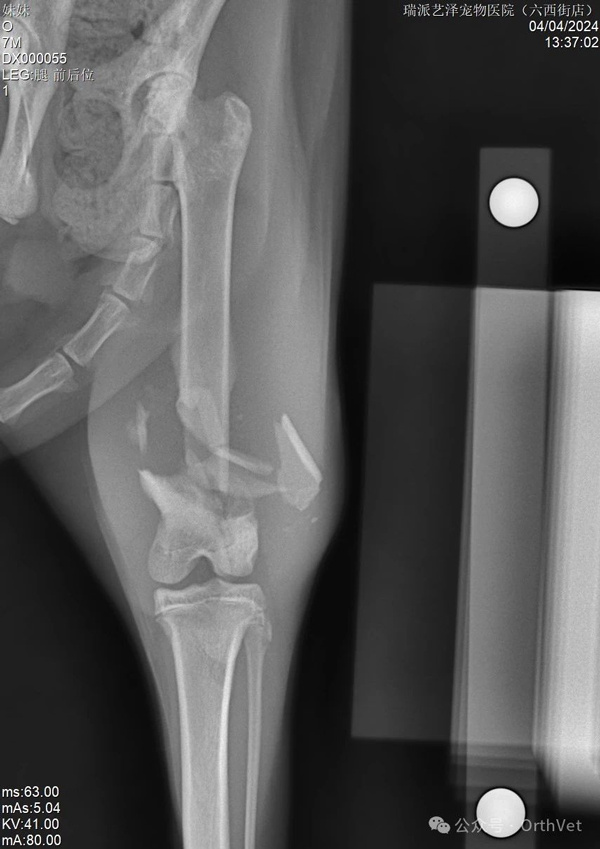

意外事故時有發生,導致各種災難性的後果。有時我們可以救治,但很多時候我們卻無能為力。這隻貓從高處跳下,遭受了嚴重的粉碎性骨折。手術的困難在於:幼貓需要考慮股骨的生長問題。幸運的是,6個月以上年齡的貓,股骨遠端生長板已經沒有太多剩餘的生長空間。其次,也要考慮動物術後無法有效限制運動,這涉及到股骨遠端髕股滑車和膝關節的活動。所採用的固定結構要考慮生長、機械穩定性和骨癒合等因素。基於上述考慮,股骨遠端採用內外雙板固定,既穩定又能中和骨骼的軸向壓縮力。 PRCL-6.5+5mm 骨板 內外固定採用股骨乾螺絲固定。採用膝關節外側入路,延伸至股骨中部。先行股骨內側固定,內側骨板不需過多塑形,再進行外側固定。在結構和力學穩定的情況下,盡量少用螺絲,盡量採用鎖定螺絲固定。術後需加強活動,避免肌肉沾黏及股四頭肌收縮。術後可使用預防性90-90繃帶固定3-5天。

以上是術前X光片